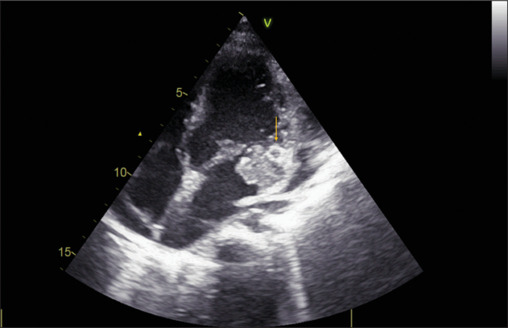

一名13岁女孩在因骨髓炎住院治疗后发生先天性二尖瓣感染性心内膜炎(IE)。临床过程中并发心肌内脓肿和严重的二尖瓣反流。嗜麦芽窄养单胞菌血培养呈阳性,这是一种罕见的IE病因,已知对用于治疗IE的一线药物具有耐药性,并有引起心肌脓肿的倾向。因此,对嗜麦芽葡萄球菌引起的心内膜炎的认识提高是有必要的。

A 13-year-old girl developed infective endocarditis (IE) on the native mitral valve after hospitalization for osteomyelitis. The clinical course was complicated by intramyocardial abscess and severe mitral regurgitation. Blood cultures were positive for Stenotrophomonas maltophilia, a rare cause of IE, which is known to be resistant to the first-line agents used for the treatment of IE, and has a propensity to cause a myocardial abscess. Hence, an increased awareness regarding endocarditis due to S. maltophilia is warranted.